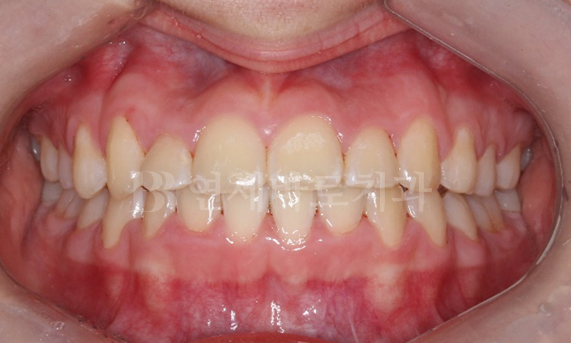

앞니 벌어짐 교정 CASE

-

연세바로치과는 치료법을 준수합니다. 로그인 하시면 Before를 보실 수 있습니다. LOGIN